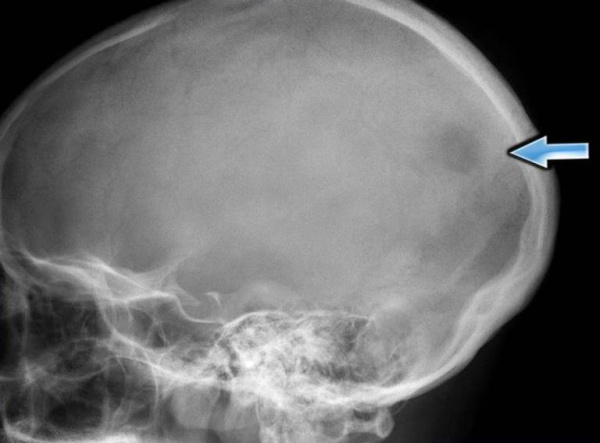

(Слева) Рисунок в боковой проекции: множественные литические очаги костей черепа, которые можно наблюдать при лантергансоклеточном гистиоцитозе (ЛКГ). Очаги имеют скошенные края, указывающие на неравномерное поражение внутренней и наружной пластинок костей черепа.

(Справа) Рентгенография черепа в ПЗ проекции: типичная скошенность краев патологических очагов при классическом ЛКГ. Скошенность краев не является патогномоничной для ЛКГ, однако этот признак типичен и при наличии имеет высокую ценность. Кроме того, визуализируется секвестр, что является еще одним типичным признаком данного заболевания. (Слева) Рентгенография в косой проекции, выполненная тангенциально выпуклости на черепе: визуализируется литический очаг, занимающий диплоитическое пространство и характеризующийся скошенным краем. Такая картина типична для ЛКГ, особенно у детей.

• Краниография:

о Позволяет обнаружить поражения черепа:

- «Выштампованные», относительно хорошо отграниченные

- Очаги могут иметь неправильную форму и больший размер, иногда создавая картину «географического черепа»

(Слева) На краниограмме в боковой проекции у ребенка с хроническим диссеминированным ЛКГ визуализируются типичные мелкие «выштампованные» просветления.